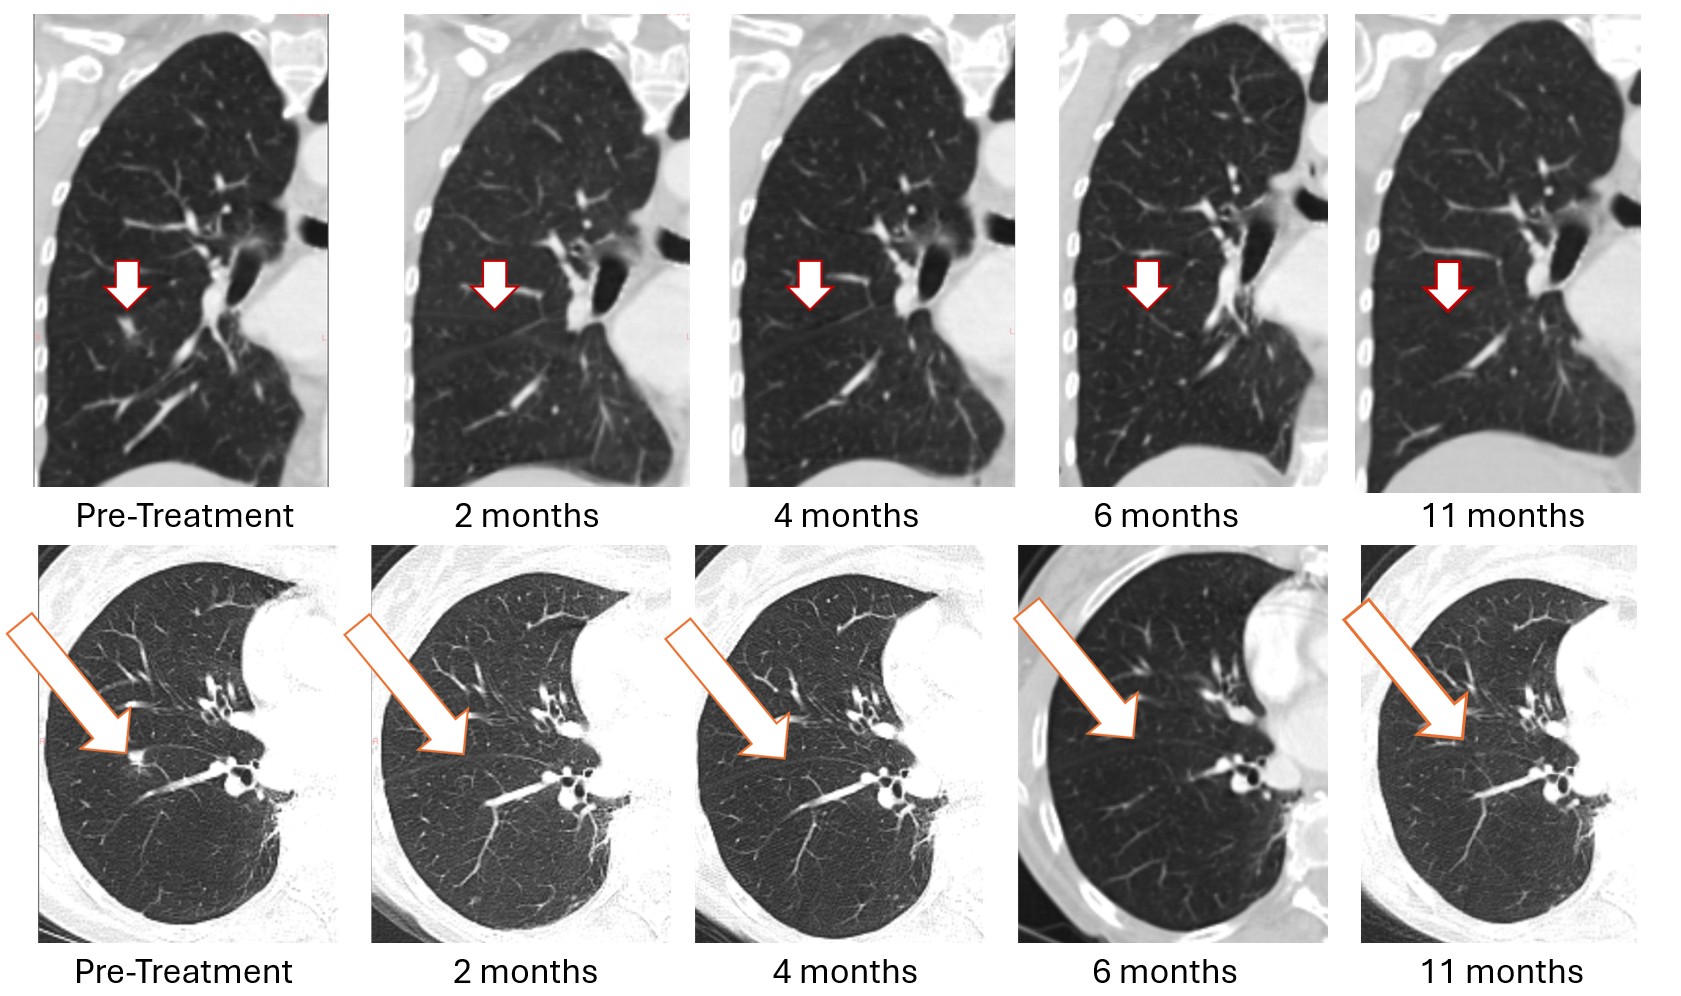

The first patient enrolled in the Bria-OTS study, a 78-year-old woman with advanced metastatic breast cancer and multiple prior treatment failures, achieved complete (100%) resolution of a lung metastasis following four doses of Bria-OTS single agent therapy. The complete response, initially observed at 2 months (previously reported), was subsequently confirmed at 4 months (previously reported), 6 months (previously reported), and now at 11 months. The patient received 17 cycles of Bria-OTS, completed 12 months of the study, and remains in survival follow-up.

Figure 1: Treatment with Bria-OTS monotherapy resulted in 100% resolution of tumor in the right lung of the metastatic breast cancer (MBC) patient following 2 months of therapy and confirmed at 4, 6, and 11 months of therapy1 (axial and coronal views)

1 Note that the other white dots in the lungs are blood vessels.